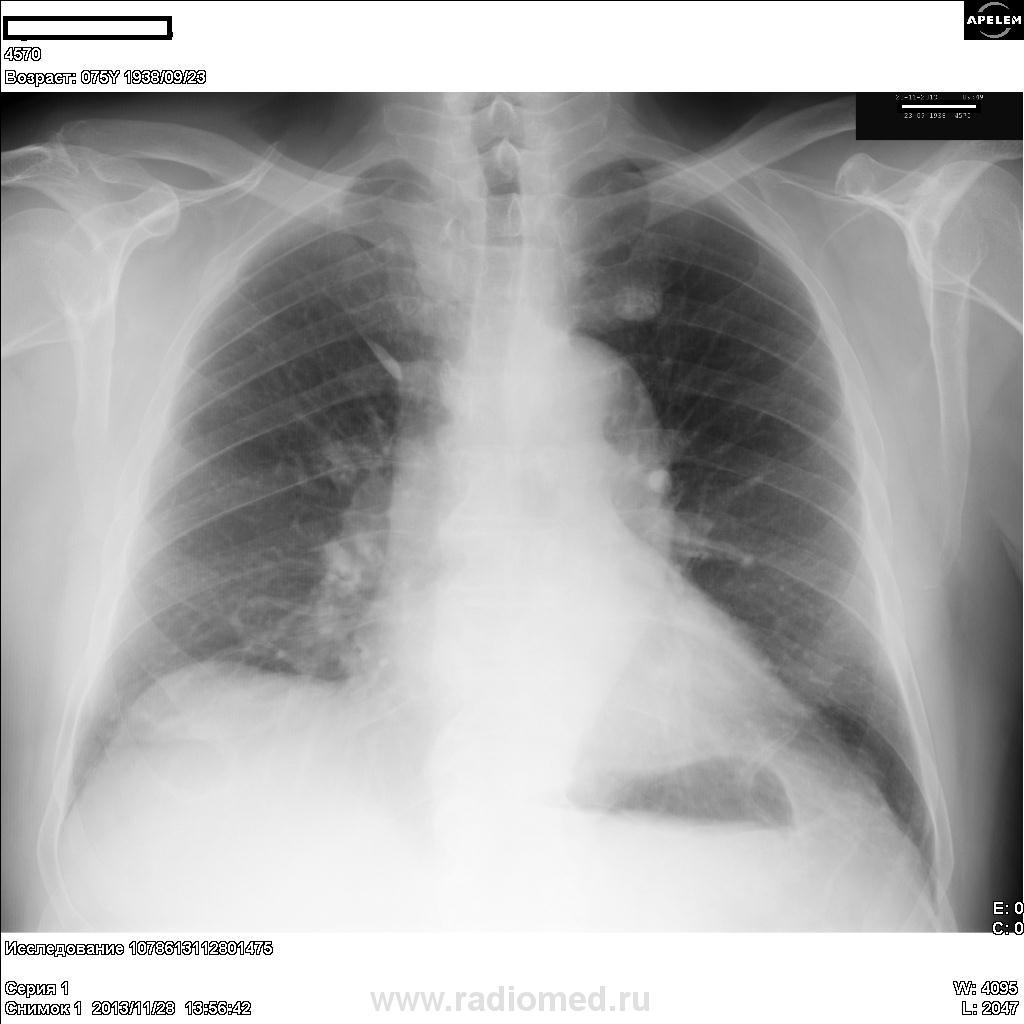

Думаю, что в в/доле справа тень добавочной доли непарной вены (зелёная стрелка), в в/доле слева на уровне I ребра обызвествление рёбернохрящевого сочленения(жёлтая стрелка), а вот затемнение в н/доле слева (красная стрелка) настораживает

С зеленой стрелочкой согласен. Красная - думаю усиление корня. Жёлтая- на мой взгляд с ребром непосредственно не связана, хотя почти вплотную к ребру, и расположена субплеврально.

А мне нижняя доля слева продолжает не нравиться, видится перибронхиальная муфта. Сравните с боковушками на соседних ветках, там такого в хвосте корня нет.

Если без косой проекции, Максималист, что же можно было заключить? Мое мнение между туберкулемой и кальцинированной гематомой, уж больно "кругленькая" тень. Вы таки все же присоединяетесь к обызвесвлению реберно-хрящевого сочленения?

Что - то в верхней доле не нравится мне тенюха, предложил бы порезать на линейке. На туберкулому тянет. Дмитрий, не делали ли вы скопию?

Остеома ребра?

Больше склонясь к образованию остеофитов в месте костно-хрящевого перехода, с реакцией плевры.

Здесь Валентин Львович оценил это как избыточное окостенение, связанное с перенесенной ранее травмой. Спасибо, NIL, за ссылку.